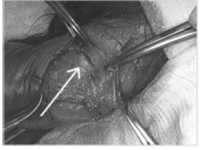

전공의핸드북 그림19.png

백색막의 손상이 관찰되고 있다.